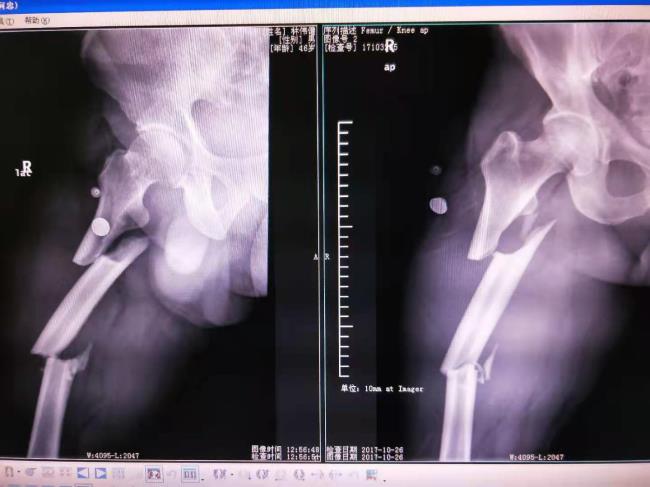

中医药结合桥接系统生物内固定技术

中医药结合桥接系统生物内固定技术治疗四肢骨折固定牢固,骨折愈合快,能早期康复,获广西医药卫生事宜技术推广奖三等奖。

病例2、左股骨骨不连治前及治疗后X线片